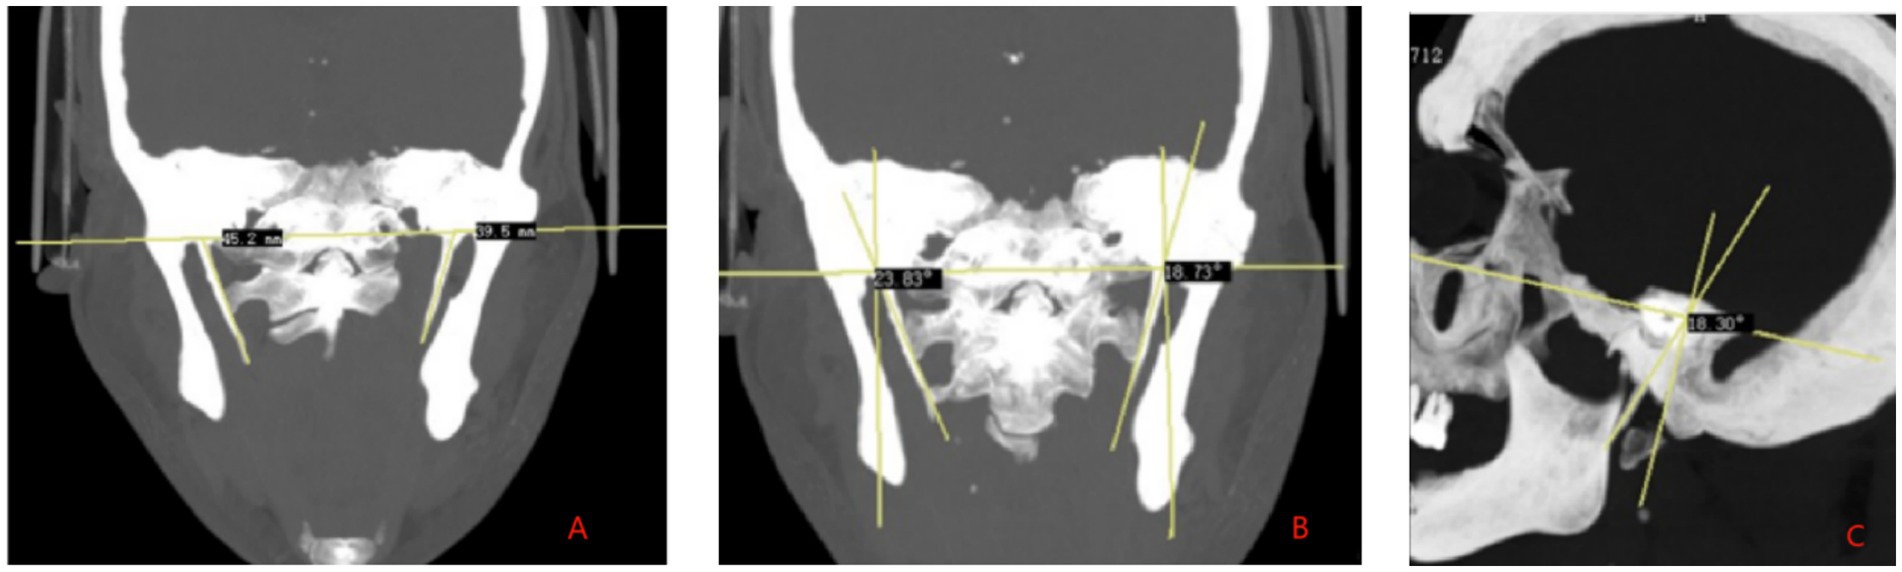

SP length measurement: The distance from the center of the SP root to the tip of the SP was measured on the CT reconstructed images, which is defined as the SP length (Figure 2A). SP angles: (1) Inward angulation: The reconstructed MIP image in the coronal plane clearly display the bilateral SP roots and tips. The angle between the long axis of the SP and the perpendicular line to the cranial base plane was measured (Figure 2B). (2) Forward tilt: The MIP image in the sagittal plane clearly showed one side of the SP and the inferior margin of the orbit, and the angle between the long axis of the SP and the inferior orbital margin and the internal ear cochlea was measured (Figure 2C). If the SP is curved or segmented during measurement, the long axis is defined as the line connecting the midpoint of the SP root and the midpoint of the distal end. Head index measurement: The maximum transverse diameter (biparietal diameter) and maximum anteroposterior diameter (occipitofrontal diameter) of the skull are measured. The head index is calculated using the formula: (transverse diameter of the skul/anteroposterior diameter of the skull) × 100 (15, 16).

Figure 2. High-resolution CT three-dimensional reconstruction maximum density projection. (A) SP length measurement. (B) SP measurement of medial declination angle. (C) SP measurement of anterior inclination angle.